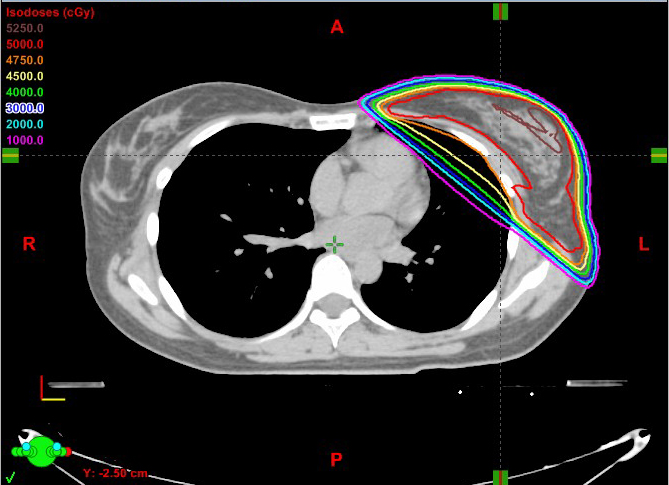

女性 36歳

左乳がん 術後照射

66Gy/33回

線量分布図